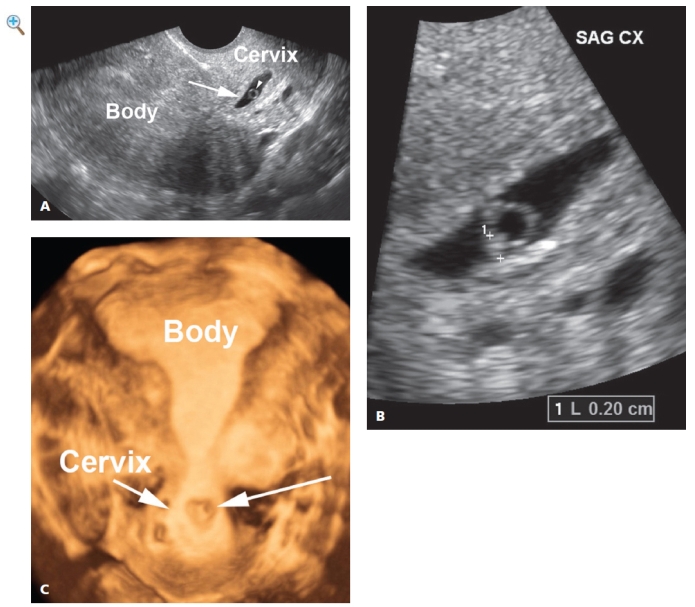

With cervical ectopic pregnancy, ultrasound demonstrates a gestational sac in the cervix, often containing a yolk sac or embryo (Figures 32.3.1 and 32.3.2). Two diagnostic dilemmas can arise in the sonographic diagnosis of cervical ectopic pregnancy: (1) distinguishing between cervical ectopic pregnancy and a miscarriage in progress and (2) distinguishing between a sac implanted in the cervix and one implanted in the lower uterine segment. The first distinction can usually be made based on the appearance of the intracervical gestational sac. A well-formed, round or oval sac surrounded by a thick echogenic rim is highly suggestive of cervical ectopic pregnancy, particularly if an embryo with cardiac activity is seen within the sac. On the other hand, a gestational sac that began in the uterine body and is in the process of passing through the cervix is typically flattened, has little or no echogenic rim, and is empty or has a dead embryo within it. When there is uncertainty about the correct diagnosis, rescanning a day or two later will generally clarify the matter: an unchanged appearance is indicative of cervical ectopic pregnancy, whereas the disappearance or marked change in appearance of the sac indicates a miscarriage in progress.

Distinguishing between cervical and lower segment implantation can usually be made by transvaginal ultrasound based on the distance between the gestational sac and the transducer. With cervical ectopic pregnancy, the sac is generally within 1–2 cm of the transducer

FIGURE 32.3.1 Cervical ectopic pregnancy on transvaginal sonography. A: Sagittal transvaginal view of the uterus demonstrates a gestational sac (arrow) with yolk sac (arrowhead). The gestational sac lies within the cervix, not the body of the uterus. B: Close-up view of the embryo (calipers) within the intracervical gestational sac. Embryonic cardiac activity was seen on real-time sonography. C: 3D image demonstrates the gestational sac (long arrow) within the cervix (short arrow), and not in the uterine body. D: Video clip showing embryonic cardiac activity within the cervical ectopic pregnancy.